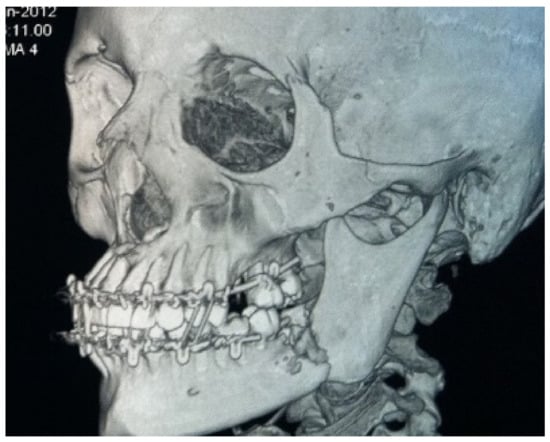

Multi-spiral computed tomography of the lower jaw determined an oval-shaped bone lesion at the root level of teeth 3.7 and 3.8, with dimensions of 20 × 16 × 16 mm. The bone was swollen at the level of teeth 3.6–3.8, a periosteal reaction was noted, the contours of the jaw were enlarged, and the cortical plates were thinned. Pathological fracture of the lower jaw, with fragment displacement, occurred; the fracture line passed through the sockets of teeth 3.7 and 3.8 (Figure 2).

Figure 2.

Patient’s CBCT at admission.